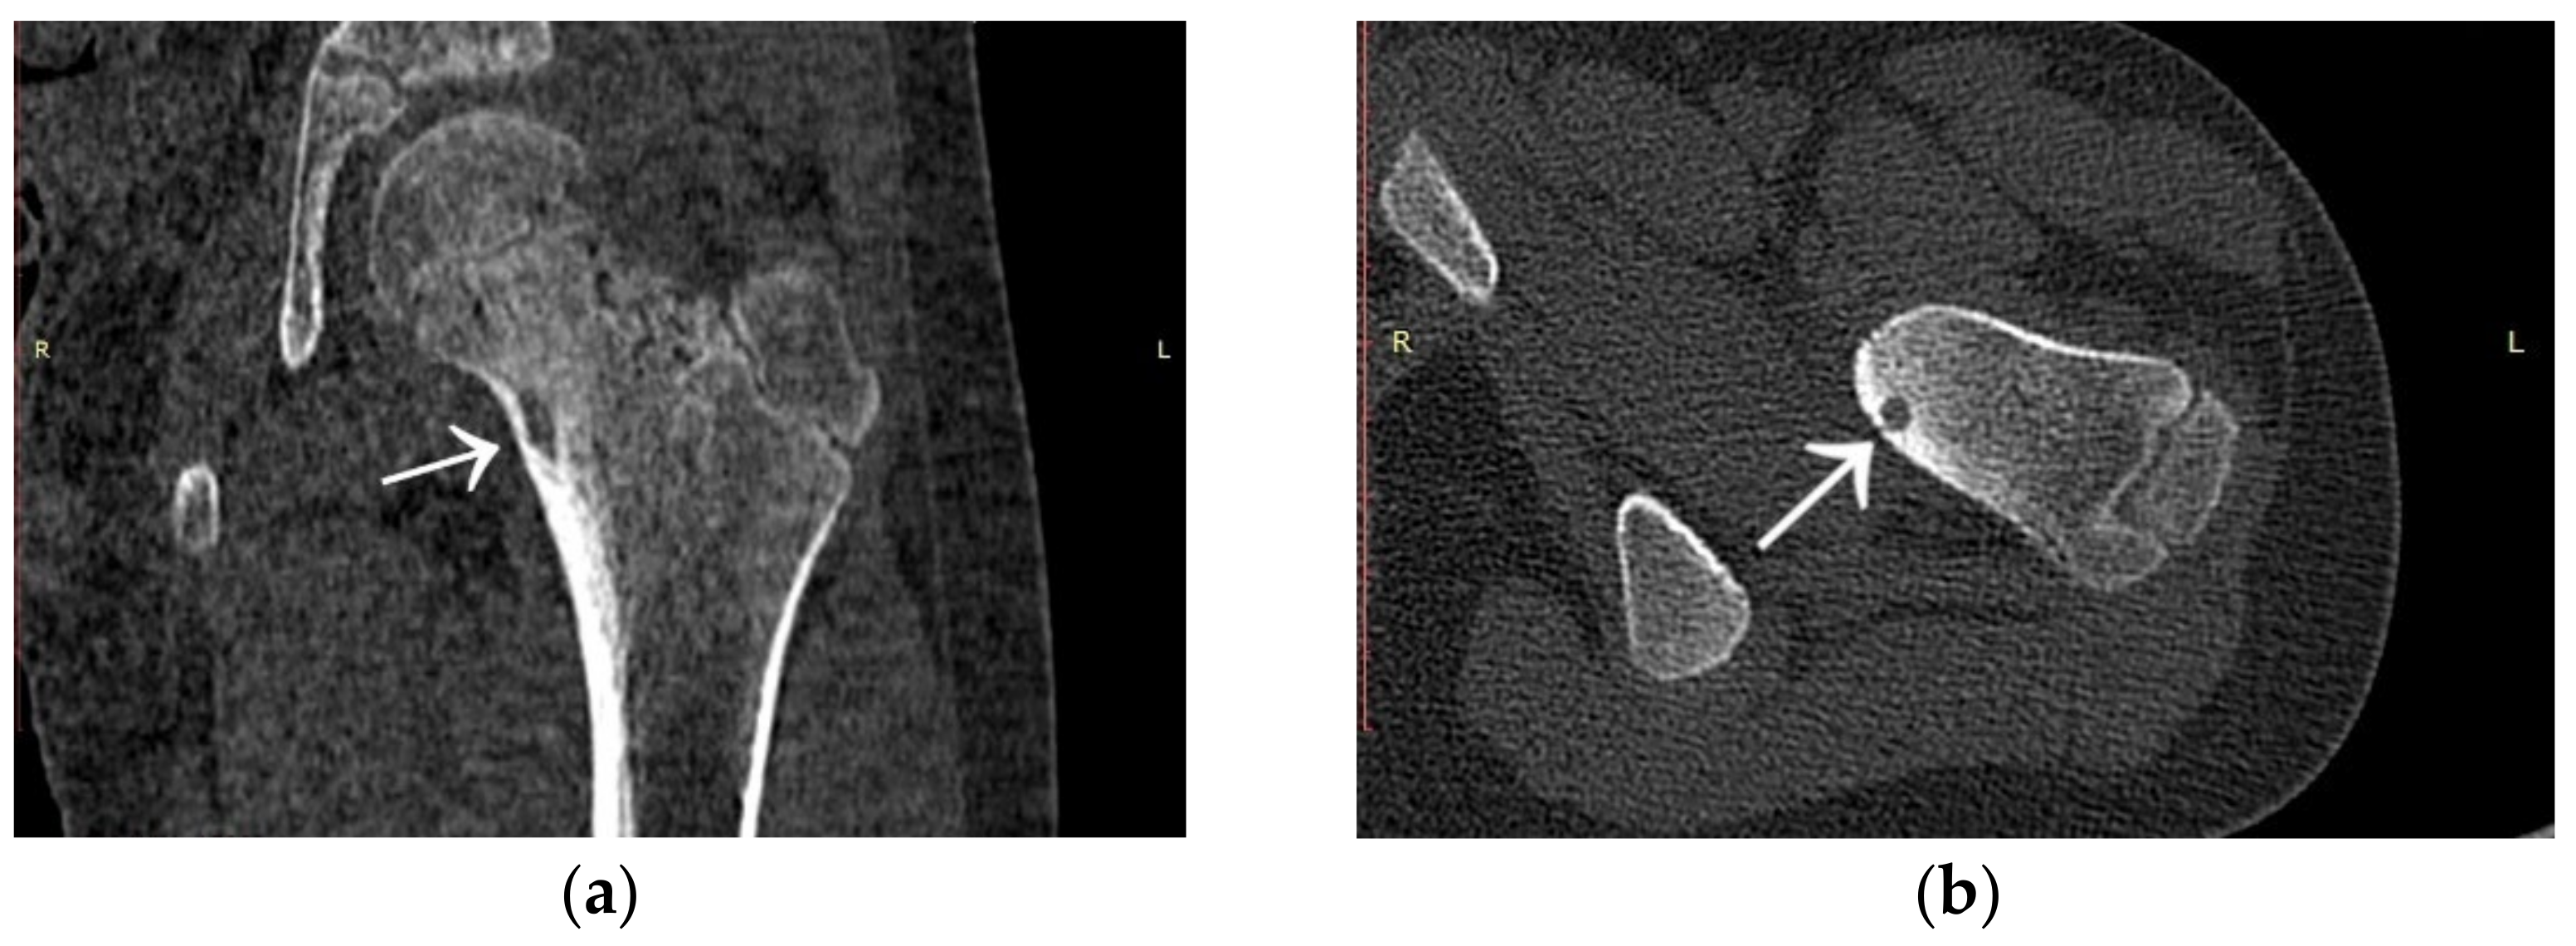

3.4. Case 4: OO Masking as a Fatigue Fracture

3.5. Case 5: OO Masking as Tuberculosis and Juvenile Idiopathic Arthritis